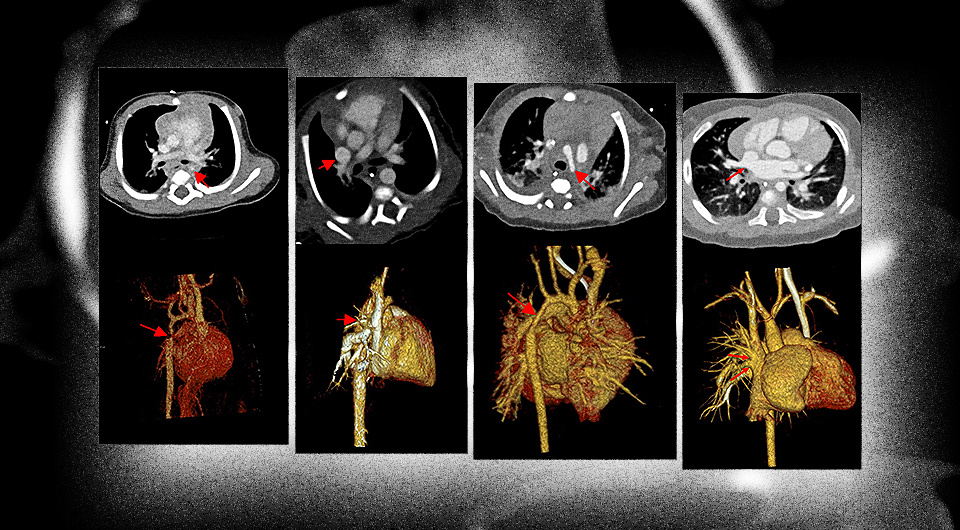

Для подробного изучения сложных пороков используют магнитно-резонансную томографию и компьютерную томографию. Хотя МРТ обладает явным преимуществом по сравнению с КТ — оно не связано с ионизирующим излучением — метод требует полного обездвиживания пациента, что у новорожденного и грудного ребенка можно достичь лишь с помощью наркоза, а это создает дополнительные риски. Из-за этого врачи стараются разработать методы визуализации сердца у детей раннего возраста, которые бы требовали меньше наркоза или с невысокой дозой облучения.